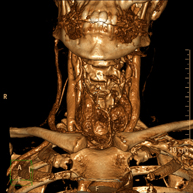

- TC Cuello Prueba radiológica que consiste en obtener imágenes del cuello de alta definición anatómica mediante el empleo de un equipo de TC (Tomografía Computarizada). Indicaciones: estudio de tiroides, control de tumores tratados, estudio de ganglios, infecciones y abscesos. Prueba radiológica que consiste en obtener imágenes del cuello de alta definición anatómica mediante el empleo de un equipo de TC (Tomografía Computarizada). Indicaciones: estudio de tiroides, control de tumores tratados, estudio de ganglios, infecciones y abscesos.

- Angio – TC Troncos Supraaórticos Prueba radiológica que consiste en obtener imágenes de las arterias carótidas del cuello de alta definición anatómica mediante el empleo de un equipo de TC (Tomografía Computarizada) y la inyección de contraste intravenoso. Posteriormente, las imágenes son reconstruidas en tres dimensiones (3D). Indicaciones: accidente vascular cerebral agudo, accidente vascular transitorio, soplo carotídeo. Prueba radiológica que consiste en obtener imágenes de las arterias carótidas del cuello de alta definición anatómica mediante el empleo de un equipo de TC (Tomografía Computarizada) y la inyección de contraste intravenoso. Posteriormente, las imágenes son reconstruidas en tres dimensiones (3D). Indicaciones: accidente vascular cerebral agudo, accidente vascular transitorio, soplo carotídeo.